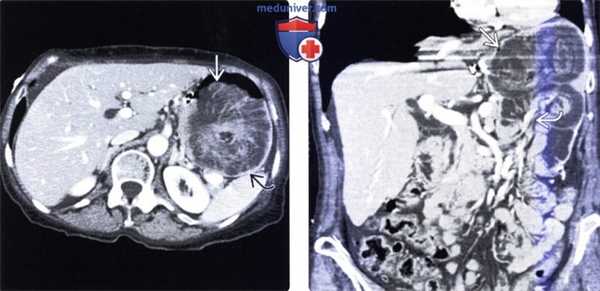

(Слева) На аксиальной КТ без контрастного усиления, выполненной женщине 83 лет, определяется, что желудок целиком располагается в грудной полости, что соответствует околопищеводной грыже четвертого типа.

(Справа) На корональной нативной КТ у этой же пациентки определяется, что желудок скручен вдоль своей длинной оси, а большая кривизна находится выше малой, что соответствует органоаксиальному завороту. (Слева) На рентгенограмме, полученной в положении стоя у женщины 80 лет, у которой были только симптомы рефлюкса, при рентгеноскопии визуализируется растянутый желудок, находящийся в грудной полости (околопищеводная грыжа, четвертый тип), определяется его органоаксиальный заворот. Просвет двенадцатиперстной кишки сужен в области перехода в брюшную полость.

(Слева) На рентгенограмме, полученной в положении лежа на спине пожилой женщине с выраженной рвотой с примесью крови, визуализируется растянутый газом, патологически измененный желудок, а также признаки ретрокардиального объемного воздействия.

(Справа) На ориентировочной (перед выполнением КТ) цифровой рентгенограмме в боковой проекции у этой же пациентки визуализируются два уровня «жидкость-газ» в желудке, а также тень, имеющая интенсивность, соответствующую жидкости, расположенная ретрокар-диально. (Слева) На КТ с контрастным усилением у этой же пациентки определяется большая около-пищеводная грыжа третьего типа: растянутый желудок с наличием жидкого содержимого, выпавший в грудную полость. Также определяется пневматоз стенки желудка, что свидетельствует о ишемическом поражении.

(Справа) На другом КТ срезе в этом же случае в растянутом желудке визуализируются два уровня «жидкость-газ», расположенные отдельно друг от друга, а также включения газа в стенке желудка. Скопление жидкости и газа большего размера находится в области тела и антрального отдела, расположенных в грудной полости, в то время как меньшее скопление располагается в области дна желудка, находящегося в брюшной полости. (Слева) На более каудальном КТ срезе, относящемся к этому же случаю, определяется пневматоз дна желудка.

(Справа) На еще более каудальном КТ срезе у этой же пациентки определяется двенадцатиперстная кишка и тонкая кишка, спавшиеся в результате ущемленного заворота желудка. На операции были подтверждены заворот и инфаркт желудка.